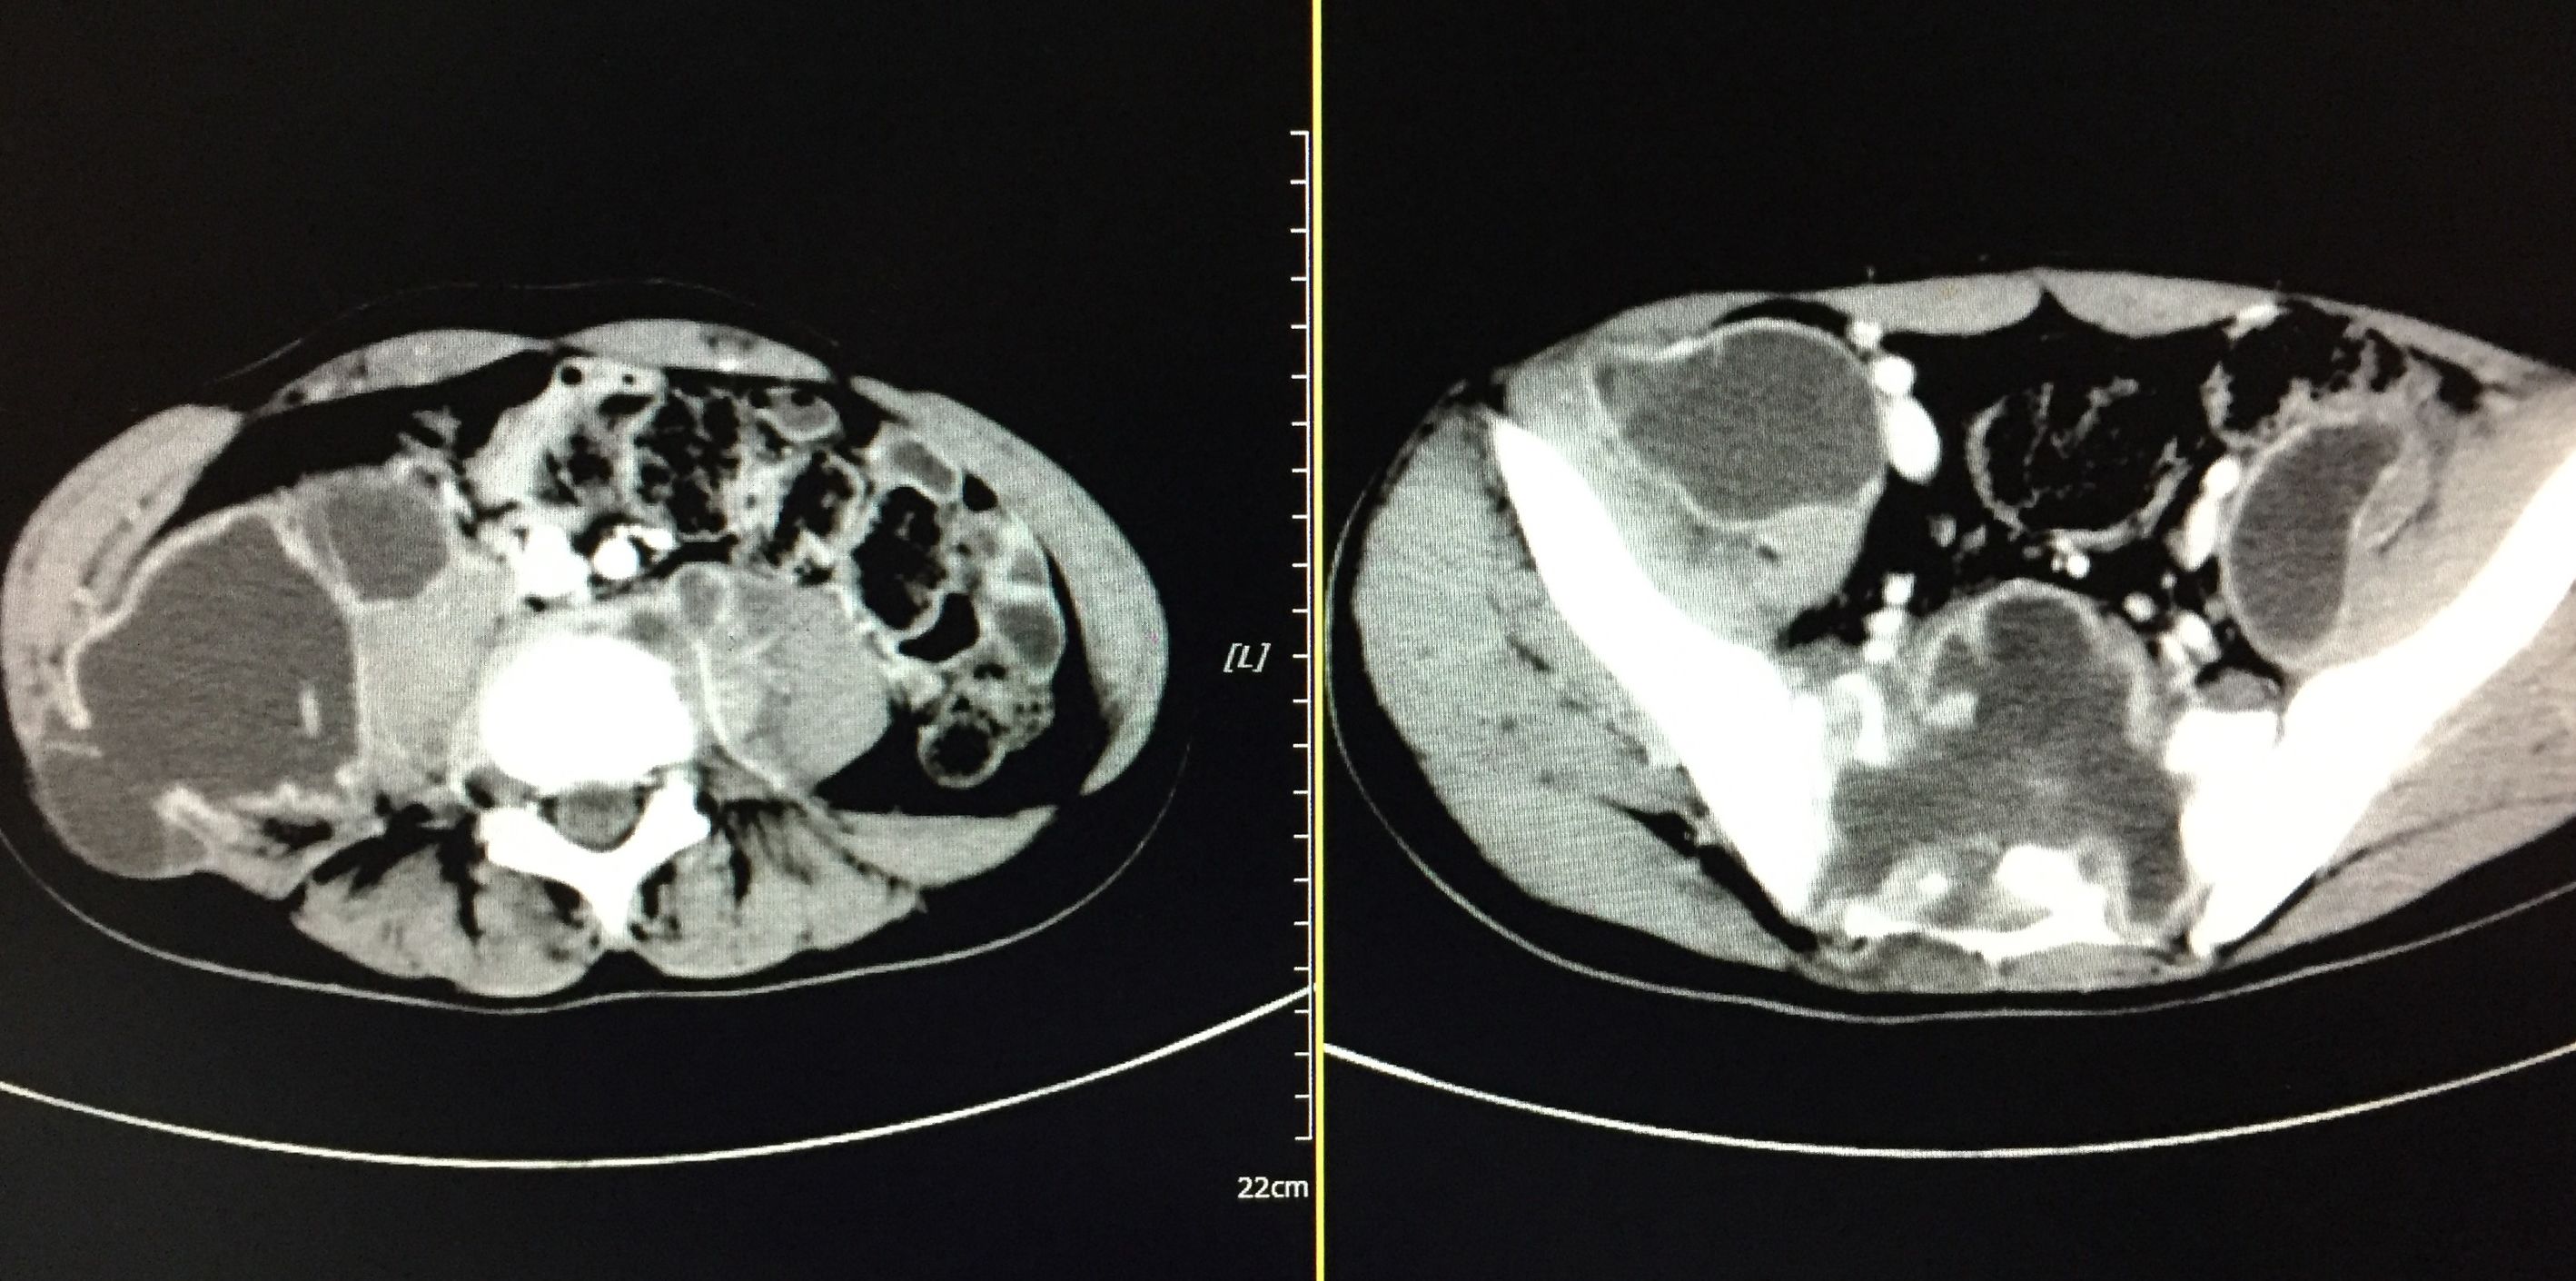

患者 20岁,低热、盗汗半年余,腰骶部疼痛。CT显示盆腔多发结核脓肿,同时骶骨骨质基本破坏,骨盆力学结构受损。

我们对患者在门诊进行充份置管引流(白色条状物5根)

在患者持续引流态势下,并联合抗痨治疗。如下图所示,脓肿完全吸收。患者痊愈。